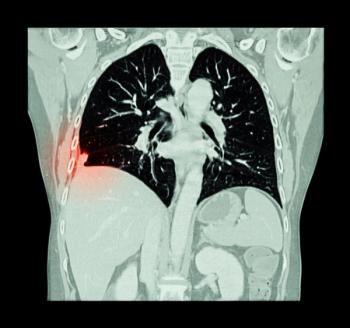

Based on a single existing chest X-ray image, the deep learning model predicts future major adverse cardiovascular events with similar performance to an established risk scoring system and may help identify people for preventive use of statin medication.